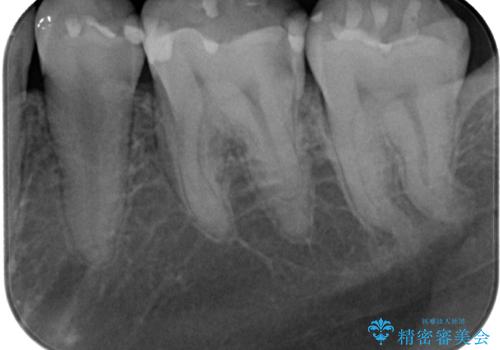

- 当院で矯正治療を終えて、左下が虫歯になっている気がするとのことで来院された患者様です。レントゲン検査の結果、コンポジットレジンによる修復箇所が複数行われており、詰め物の下に虫歯を認めました。